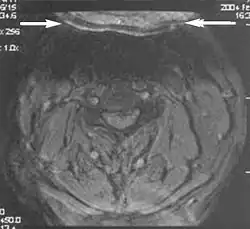

Metal artifacts occur at interfaces of tissues with different magnetic susceptibilities, which cause local magnetic fields to distort the external magnetic field. This distortion changes the precession frequency in the tissue leading to spatial mismapping of information. The degree of distortion depends on the type of metal (stainless steel having a greater distorting effect than titanium alloy), the type of interface (most striking effect at soft tissue-metal interfaces), pulse sequence and imaging parameters. Metal artifacts are caused by external ferromagnetics such as cobalt containing make-up, internal ferromagnetics such as surgical clips, spinal hardware and other orthopaedic devices, and in some cases, metallic objects swallowed by people with pica.[3] Manifestation of these artifacts is variable, including total signal loss, peripheral high signal and image distortion (Figs 3 and 4).[1] Reduction of these artifacts can be attempted by orientating the long axis of an implant or device parallel to the long axis of the external magnetic field, possible with mobile extremity imaging and an open magnet. Further methods used are choosing the appropriate frequency encoding direction, since metal artifacts are most pronounced in this direction, using smaller voxel sizes, fast imaging sequences, increased readout bandwidth and avoiding gradient-echo imaging when metal is present. A technique called MARS (metal artifact reduction sequence) applies an additional gradient, along the slice select gradient at the time the frequency encoding gradient is applied.